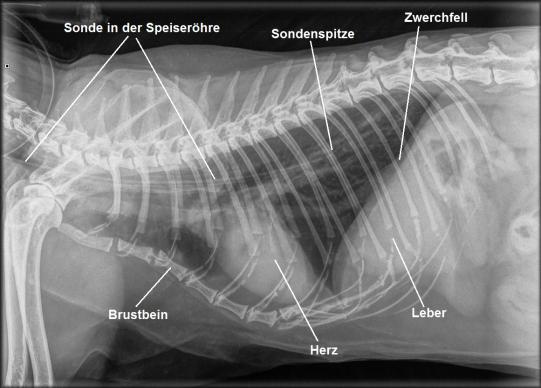

Trotz intensiver Schmerztherapie frisst Emily weiterhin nicht, auch wenn die Fütterung von Hand und etwas forciert erfolgt. Um auszuschliessen, dass ausser der Zungenverletzung noch eine andere Problematik vorhanden wäre, wird ein Bruströntgen angefertigt und Blut untersucht - beide Untersuchungen sind aber unauffällig. Ganz offensichtlich hindert allein der Schmerz der verletzten Zunge die Katze am Fressen. Obwohl Emily schon eine ältere Dame ist, entscheidet sich die Besitzerin für eine Intensivierung der Therapie: Unter einer kurzen Narkose wird eine Ernährungssonde in einem kurzen chirurgischen Eingriff in die Speiseröhre eingesetzt, über welche die Katze nun problemlos mit Nährstoffen, Medikamenten und Flüssigkeit versorgt werden kann. Der korrekte Sitz der Ösophagussonde wird mittels Röntgen kontrolliert und der Schlauch in einen Halsverband eingepackt. Der tägliche Kalorienbedarf der Katze wird berechnet, und die Besitzerin wird in der Verabreichung der Flüssignahrung über die Sonde geschult. Anschliessend wird die Katze mit Schmerzmitteln und Antibiotika nach Hause entlassen.

Die sogenannte Ösophagussonde (Ösophagus = Speiseröhre) ist eine elegante und wenig aufwendige Methode, Katzen bei Nahrungsverweigerung mit Nährstoffen und Flüssigkeit zu versorgen. In einer kurzen Narkose wird mit Hilfe eines speziellen Applikators durch einen kleinen Schnitt in der linken Halsseite ein dünner Schlauch in die Speiseröhre eingeführt. Die Sondenspitze sollte nicht bis in den Magen reichen, da sonst Magensäure durch den ständig offenstehenden Schliessmuskel in die Speiseröhre gelangen würde. Dieser Sondentyp ist der v.A. früher verwendeten Nasen-Schlundsonde (bei der ein noch dünnerer Schlauch über die Nase in die Speiseröhre geführt wird) weit überlegen: Der Durchmesser des Schlauches ist viel grösser, was die Fütterung erleichtert und eine Pflege durch die Besitzer zu Hause ermöglicht; ausserdem ist der Tragekomfort für die Katze viel grösser, da bei einer Nasen-Schlundsonde ein Halskragen getragen werden muss und ein Fremkörpergefühl in der Nasenhöhle besteht.